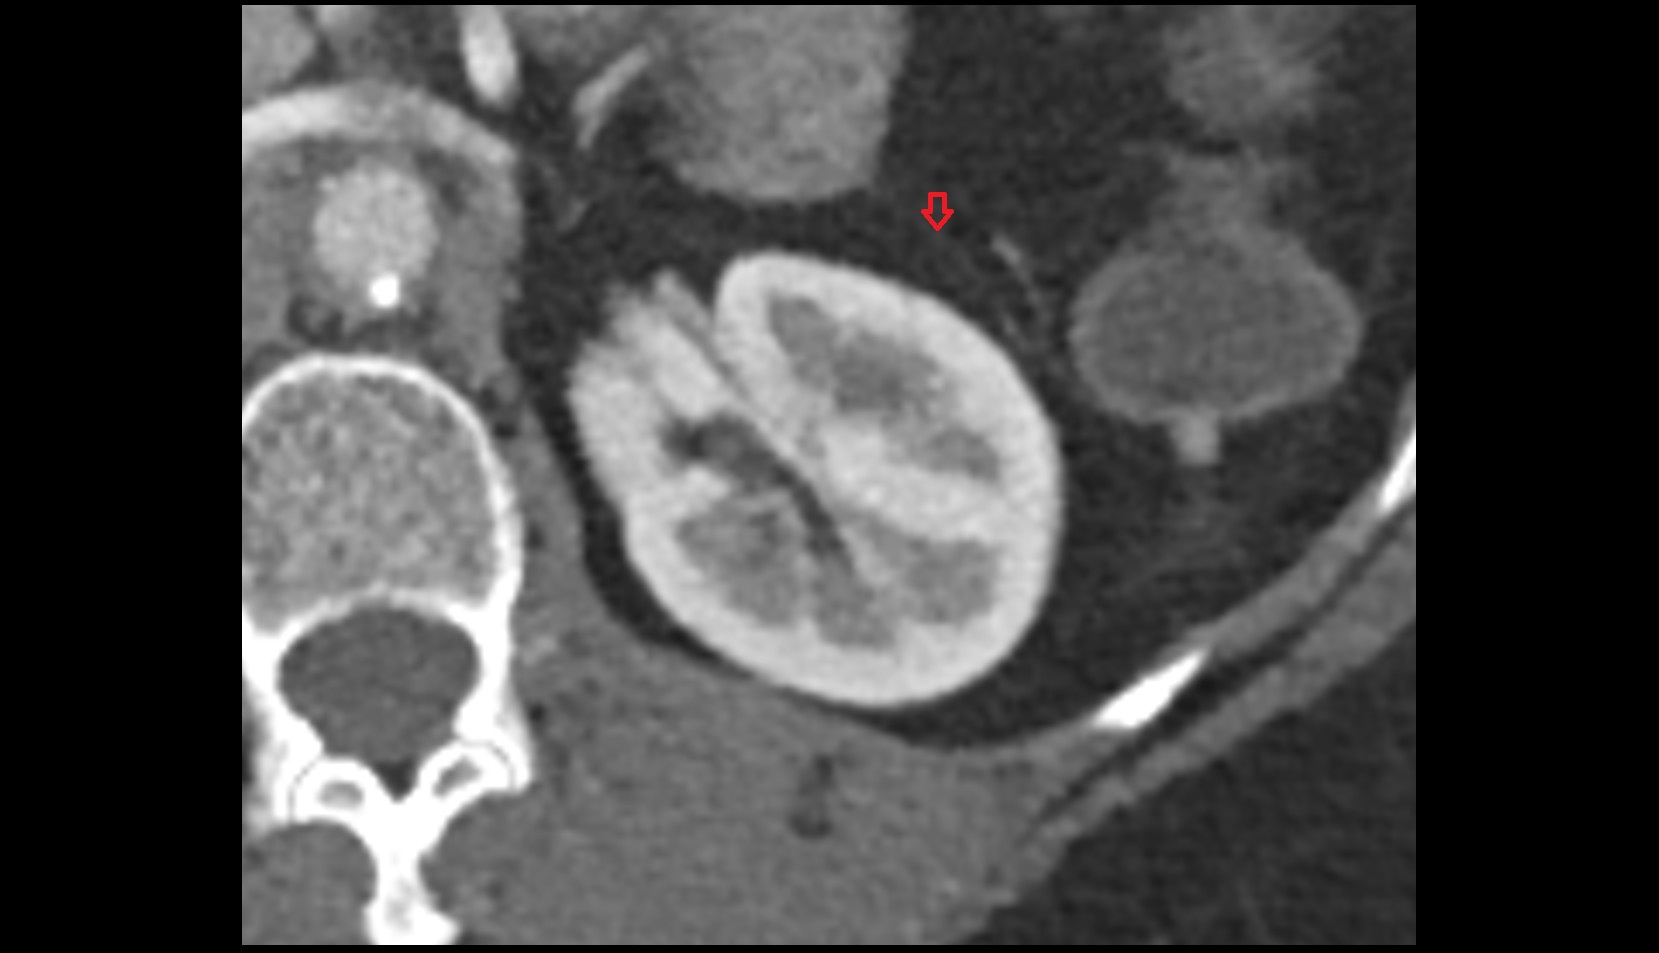

- kidneys

- Right kidney

- Left kidney

- Kidney cortex (Renal cortex)

- Renal capsule

- Renal medulla

- Renal pyramids

- Renal artery

- Renal vein